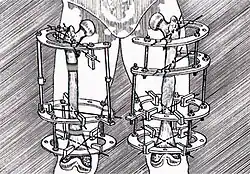

Удлинение конечностей

Для удлинения конечности, например голени, необходимо произвести остеотомию большой и малой берцовых костей, а также удлинение ахиллова сухожилия и других сухожилий мышц голени. Растяжение производится на 7–12-й день после операции на 0,25–1 мм ежедневно. После удлинения конечности на нужную величину её фиксируют в том же аппарате для консолидации (приблизительно на 3 месяца от момента операции)[2].